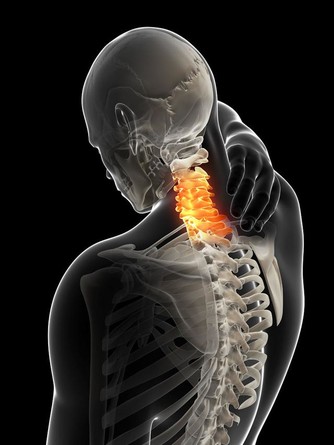

症狀4.手指疼痛、發麻,甚至手臂發麻初步診斷:頸椎病

頸椎病也可引起手指疼痛,時間長了還可能出現手指或手臂發麻。

盧振和教授說,“比較常見的原因是頸部肌肉損傷導致反復水腫、滲出、鈣化,最後變成骨刺壓迫附近的神經;另一個常見原因是頸椎間盤向後突出,對周圍神經也會形成壓迫。”

“但疼痛說明還處在炎症的階段,容易消除,若到了發麻的時候,則說明壓迫已造成缺血,問題就嚴重多了。”

應對方法:正規治療,糾正用頸的習慣:不要躺著看電視、看書;不要長時間玩電腦、打麻將;無論做什麼,30-40分鐘就變換一下姿勢,絕不能長時間固定不動。

選好枕頭。建議睡有弧度的健康枕,把脖子托起來。

時常做做頸部肌肉的對抗性鍛煉,如兩手交叉托住後腦勺,頭盡力往後仰的同時手盡力往前拉送,或一手托住頭的一側,頭往下低的同時,手往上頂。

特別注意:許多頸椎病患者喜歡做頭部米字操,但米字操動作幅度大,並非人人適宜,如果有嚴重骨刺或椎間盤突出的人不要隨便亂做。

另外,對於突然不明原因的有手痛、手麻、頭痛症狀持續三個月以上的患者,在沒有診斷排除腫瘤之前,特別是在沒有照片之前,也不主張做手法按摩或理療,以防發生意外。